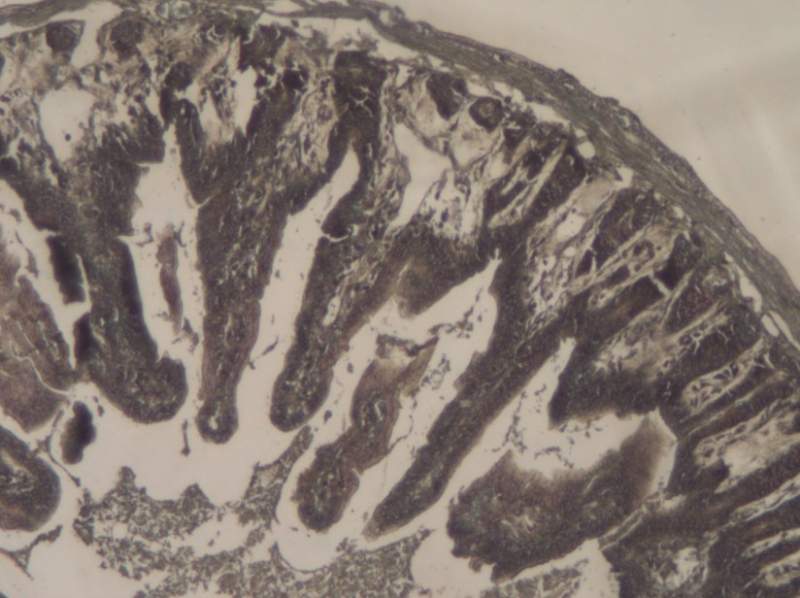

¿»ùʯÀ¯ÇÐÆ¬×¨ÓÃtunelÊÔ¼ÁºÐ×ö³öÀ´µÄСÊóµòÍö£¬½á¹ûÌØ±ð¹ÖÒ죬Çë¸ßÊÖ°ïæ·ÖÎö£¡ ÒÑÓÐ1È˲ÎÓë